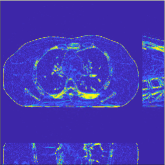

| views | ||||

|---|---|---|---|---|

| (a) , | (b) , | (c) , | (d) , |

This section compares the generalization capabilities between the proposed MBIR method, PWLS-ST-, and a denoising deep NN, FBPConvNet [14], that are trained from the phantom data; in particular, we tested the trained PWLS-ST- and FBPConvNet models to phantom and clinical scan data. The results in Fig. 6 show that the non-MBIR FBPConvNet method has higher overfitting risks, compared to the proposed PWLS-ST- MBIR method. When tested on clinical scan data, PWLS-ST- achieves much more accurate reconstruction, compared to FBPConvNet. See Fig. 6(b). When tested on phantom data, FBPConvNet generates more unnatural features as the number of views reduces, although it gives lower RMSE values compared to PWLS-ST-. See zoom-ins in Fig. 6(a). The FBPConvNet results above correspond to those in the recent work [16] that FBPConvNet [14] generated some unexpected structures.